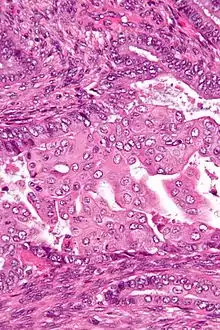

Micrograph of an atypical polypoid adenomyoma. H&E stain.

APAs are characterized by glands with abnormal shapes that: (1) often have squamous metaplasia, and (2) are surrounded by benign smooth muscle.[1] Nuclear atypia, if present, is mild.